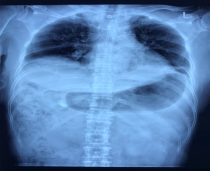

图为患者胸片,可见双侧膈肌高位

近期康复科遇到了一位这样的患者,其主要诉求就是不能平卧,夜间需要坐位睡觉,否则就会呼吸困难,日间活动也受到明显影响,爬楼2层即出现憋闷,可独立步行百米后呼吸不畅感明显。曾于外院就诊,考虑为双侧膈肌麻痹导致的呼吸困难,肺功能提示通气功能轻度减退限制型障碍。